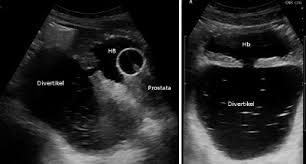

Harnblasendivertikel Ursache Diagnose Und Therapie